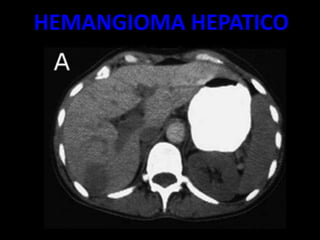

HEMANGIOMA HEPATICO

– EL MÁS FRECUENTE ES EL ANGIOMA.

SE TRATA DE UNA LESIÓN

ASINTOMÁTICO CUYA TOPOGRAFÍA

MÁS CARACTERÍSTICA ES EL

SEGMENTO POSTERIOR DEL LÓBULO

DERECHO HEPÁTICO.

– ES UNA TUMORACIÓN VASCULAR CON UNA

CIRCULACIÓN ENLENTECIDA, HIPODENSA

CON RESPECTO AL HÍGADO EN LA TC BASAL,

QUE MUESTRA UNA INTENSA CAPTACIÓN

PERIFÉRICA INICIAL TRAS LA

ADMINISTRACIÓN DE UN BOLO DE

CONTRASTE (INYECCIÓN RÁPIDA DE

CONTRASTE YO DADO A TRAVÉS DE UNA

VENA PERIFÉRICA).

• MUJERES MAS FRECUENTE

• HALLAZGOS:

– MASA HIPODENSA

– HIPERCAPTACIÒN DEL CONTRASTE 20 A 30

MINUTOS

– TRAS LA ADMINISTTRACIÒN RAPIDA DE

CONTRASTE APARECEN AREAS

NODULATRES HIPERCAPTANTES